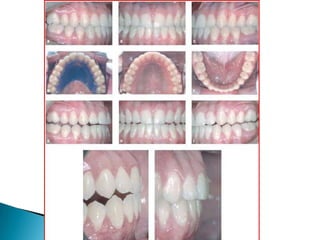

   Figura 1.,2

Figura 1.,2